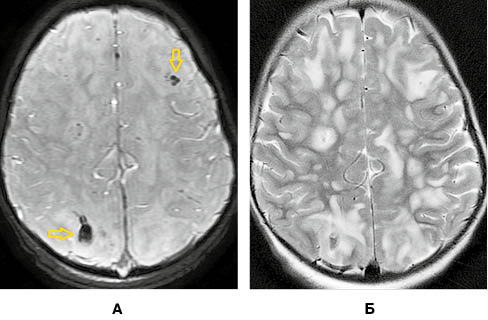

На рисунку 4 наведено МРТ-зображення головного мозку пацієнта з гострим геморагічним лейкоенцефалітом (хворобою Херста) у режимі Т2*/T2 GRE, де візуалізуються двобічні гіперінтенсивні вогнища, два з яких містять геморагічний компонент, та в режимі Т2. А на рисунку 5 — МРТ-зображення головного мозку пацієнта з ГРЕМ у режимі Т2 — продемонстровано важливу ознаку ГРЕМ (на відміну від РС): відносну інтактність мозолистого тіла, стовбура мозку, середніх мозочкових ніжок та мозочка, які в разі РС, як правило, уражаються першочергово. Вказана ознака не завжди є показовою, але має високу інформативність для диференційної діагностики.

/images/nn257-1622023r4_.jpg)

/images/nn257-1622023r5_.jpg)